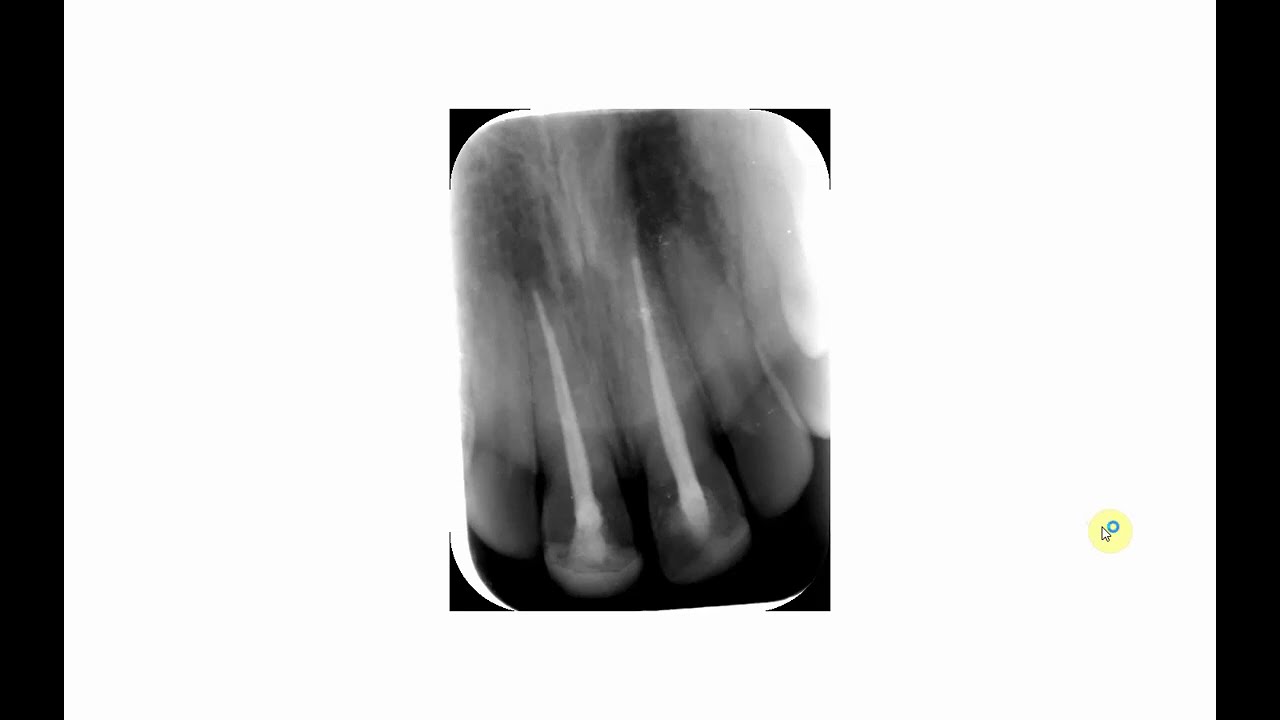

V1119 Optimizing Digital Radiography

Описание: Digital dental radiology has made major strides since its introduction many years ago. However, in spite of the obvious advantages, there are numerous challenges. This video addresses those challenges and will help you to solve them. The following are included in the instructional video:

Clinical techniques and tips for intraoral digital imaging.

Improving quality of digital images - enhancement and software tools.

In spite of most dental professionals having digital radiography, there are many challenges. This video will help dentists and staff members to reduce or eliminate them.